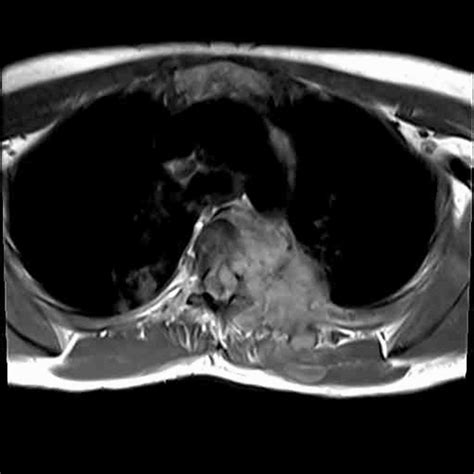

Diagnosing Pott’s disease can be a bit like detective work, guys, because, as we’ve talked about, the symptoms can be sneaky and mimic other conditions. So, doctors need to put on their Sherlock Holmes hats and gather clues from various sources. The first step, of course, is a thorough medical history and physical examination . The doctor will ask about your symptoms, their duration, any history of TB exposure or infection, your overall health, and any risk factors like immunocompromise. During the physical exam, they’ll check for tenderness over the spine, assess your range of motion, look for any deformities like a gibbus, and importantly, perform a neurological exam to check for any signs of spinal cord compression or nerve involvement – things like weakness, numbness, or reflex changes. Once the initial assessment raises suspicion, imaging studies become crucial. X-rays of the spine were traditionally the first line, and they can show abnormalities like narrowing of the disc space, destruction of the vertebral bodies (those lytic or ‘punched-out’ lesions), or evidence of collapse and deformity. However, X-rays might not pick up early changes, so more advanced imaging is often needed. CT scans (Computed Tomography) are excellent for visualizing bone detail. They can show the extent of vertebral destruction, involvement of the posterior elements of the spine, and help identify the presence and extent of any cold abscesses . MRI (Magnetic Resonance Imaging) is often considered the gold standard for diagnosing Pott’s disease. It provides detailed images of both bone and soft tissues. MRI is fantastic at showing the extent of bone marrow involvement, the degree of disc destruction, the presence and size of epidural or paravertebral abscesses (collections of pus around the spine), and importantly, it can clearly visualize spinal cord compression , which is key for surgical planning and assessing neurological risk. To confirm the diagnosis and pinpoint the exact cause, microbiological and histological examination is essential. This usually involves obtaining samples for analysis. A biopsy of the affected bone, disc, or any drained abscess fluid is taken. These samples are then sent to the lab to be cultured for Mycobacterium tuberculosis . They’ll also be examined under a microscope for characteristic inflammatory changes and the presence of acid-fast bacilli (AFB), which are the TB bacteria. Sputum microscopy and culture might also be done, even if lung symptoms aren’t prominent, to check for co-existing pulmonary TB. Blood tests , like an ESR (erythrocyte sedimentation rate) and CRP (C-reactive protein), are usually elevated, indicating inflammation, but they are non-specific. Tuberculin skin tests (TST) or interferon-gamma release assays (IGRAs) can suggest TB infection but don’t differentiate between active and latent TB, nor do they pinpoint the location of the infection. So, it’s really a combination of clinical suspicion, advanced imaging, and definitive microbiological proof that allows doctors to confidently diagnose Pott’s disease. It’s a puzzle, but putting all the pieces together is vital for effective treatment.